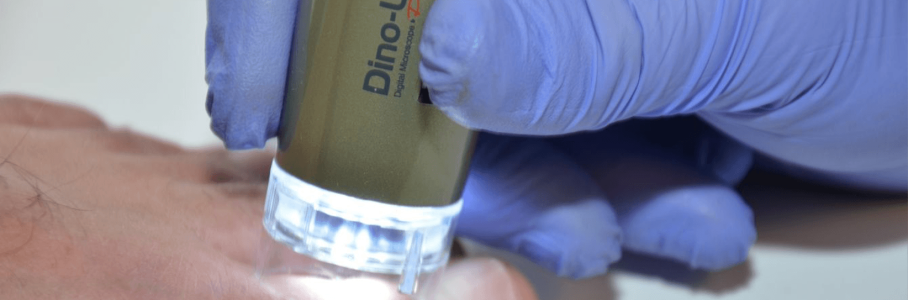

PODOLOGÍA CON UN PODOSCOPIO

El profesor Mauro Montesi es el presidente de la Asociación Italiana de Podólogos (Associazione Italiana Podologi). Actualmente, la organización cuenta con 270 miembros repartidos por toda Italia. Montesi es un gran admirador del podoscopio de Dino-Lite ya que cree que aporta una gran contribución a la profesionalización de la profesión de la podología.

El podoscopio contribuye a profesionalizar la podología

Montesi: "La ventaja principal de usar el podoscopio es que permite que los podólogos tomen imágenes de la piel del pie mediante la captura de imágenes microscópicas. De esta forma, el desarrollo clínico de una posible lesión, por ejemplo, se puede seguir con facilidad. Gracias al podoscopio, se pueden descubrir pequeñas grietas en la piel en una fase temprana, lo cual es importante, ya que las bacterias se pueden acumular en dichas grietas y, a su vez, provocar infecciones graves, con consecuencias para la movilidad del paciente. Un descubrimiento tardío podría causar incluso una neuropatía. Por lo tanto, recomendamos encarecidamente el uso del podoscopio en algunos casos. Ahora nos corresponde hacer que nuestros miembros conozcan la existencia del podoscopio y explicar que su utilización profesionalizará de manera significativa nuestra profesión".